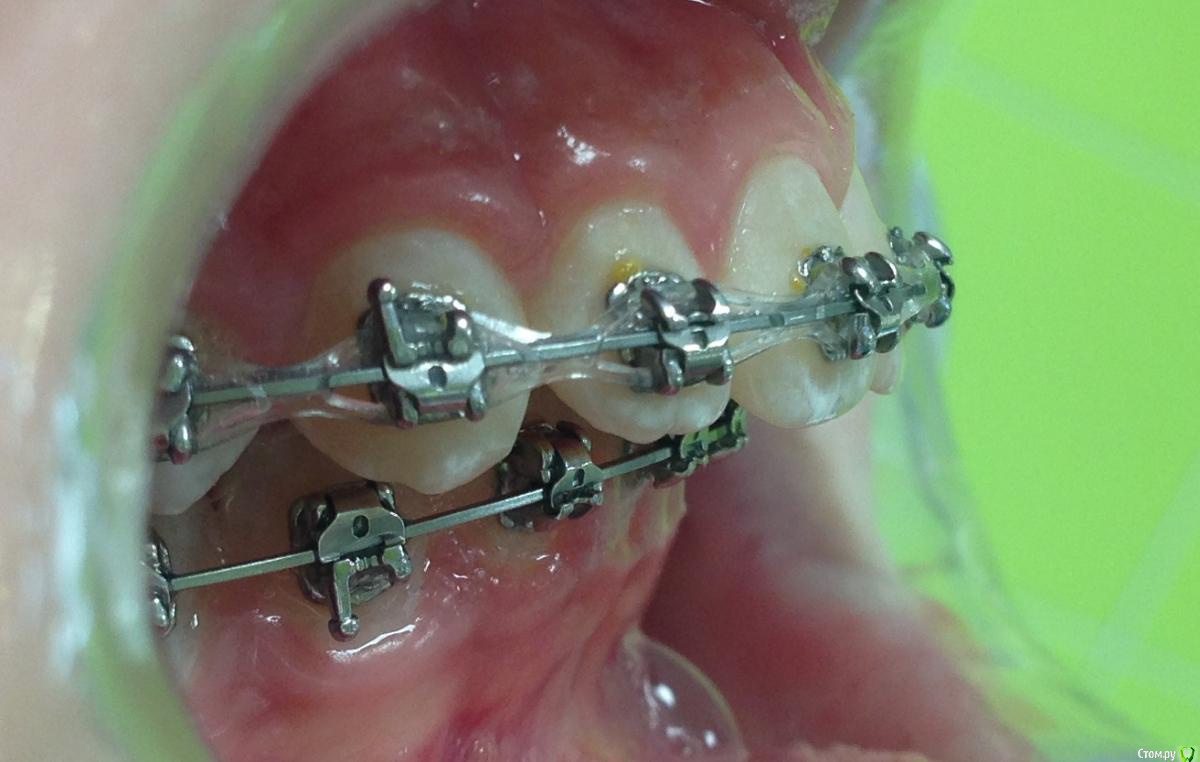

post-38874-0-87186300-1459536185_thumb.jpgpost-38874-0-15339500-1459536188_thumb.jpgpost-38874-0-82577500-1459536190_thumb.jpgpost-38874-0-61079300-1459536193_thumb.jpgpost-38874-0-22178300-1459536196_thumb.jpgpost-38874-0-56404400-1459536198_thumb.jpgpost-38874-0-43380300-1459536199_thumb.jpgpost-38874-0-04081600-1459536228_thumb.jpgpost-38874-0-34503200-1459536230_thumb.jpgpost-38874-0-34236500-1459536233_thumb.jpgpost-38874-0-95387400-1459536234_thumb.jpgpost-38874-0-86290600-1459536242_thumb.jpgpost-38874-0-47956700-1459536252_thumb.jpgpost-38874-0-98507600-1459536273_thumb.jpgpost-38874-0-52220700-1459536283_thumb.jpgpost-38874-0-12327700-1459536263_thumb.jpg

Извините за качество фото.

Пациентка 14 лет. Было принято решение лечить без удаления, тк. профиль не позволяет да и ретропозиция нч. Лечение идет. Я назначила ранние эластики слабые, на 17/25 нити на вч и 18 нити на нч. по 2 классу короткие 3,4-4,5. Пациентка пришла через месяц жалуется на щелканье челюсти во время ношения эластиков и сразу после их снятия. Т.е. если открывает рот, то челюсть скачкообразно двигается и щелчками. Последние 2 недели, когда много говорит, то вообще стала заедать. Это она так сказала. После отмены эластиков (страшно), через неделю пришла, рот открывает ровно, без девиации, щелчков нет. Вопрос: почему щелкает и что с этим делать? По поводу прикуса, посоветуйте, пожалуйста, как нормализовать? Аппарат типа гербста? может ей твинблок сделать? Эластики? К сожалению другими методами я пока что не владею. Спасибо, очень жду ваших советов.